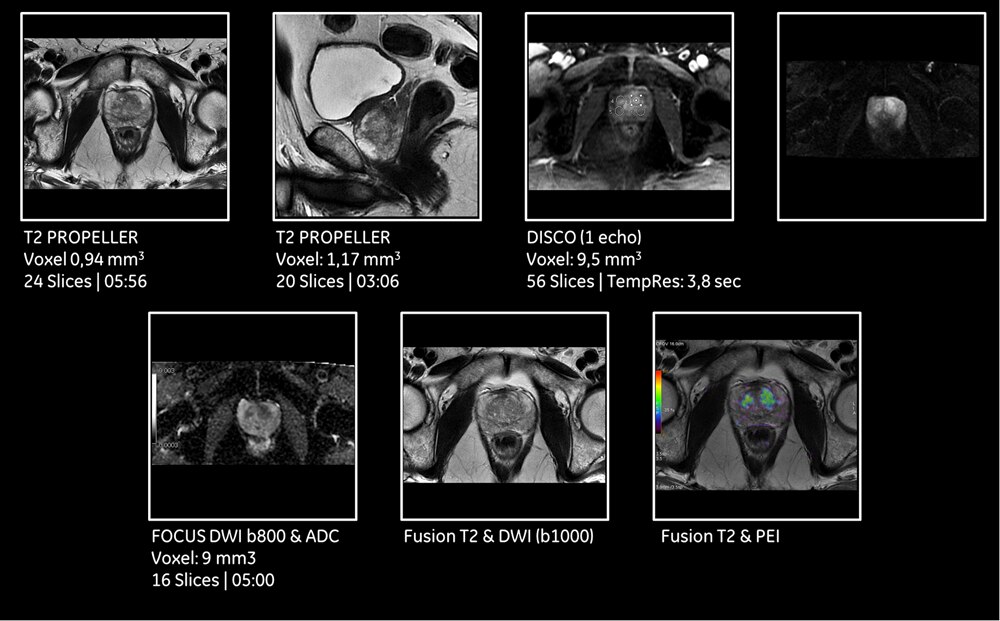

3 tesla 3t mri is particularly useful in scans of the brain and spinal column and of the musculoskeletal system. İleri görüntüleme merkezi 3 tesla mr 4d ultrason röntgen koroner bt anjiyo multiparametrik prostat mr multipametrik beyin mr 3 tesla tüm vücut mr güzelbahçe sok. 3 tesla magnetic resonance mr in the images obtained with magnetom skyra 3t mr system resolution is increased while thinner cross sections can be formed. 3 tesla mr.